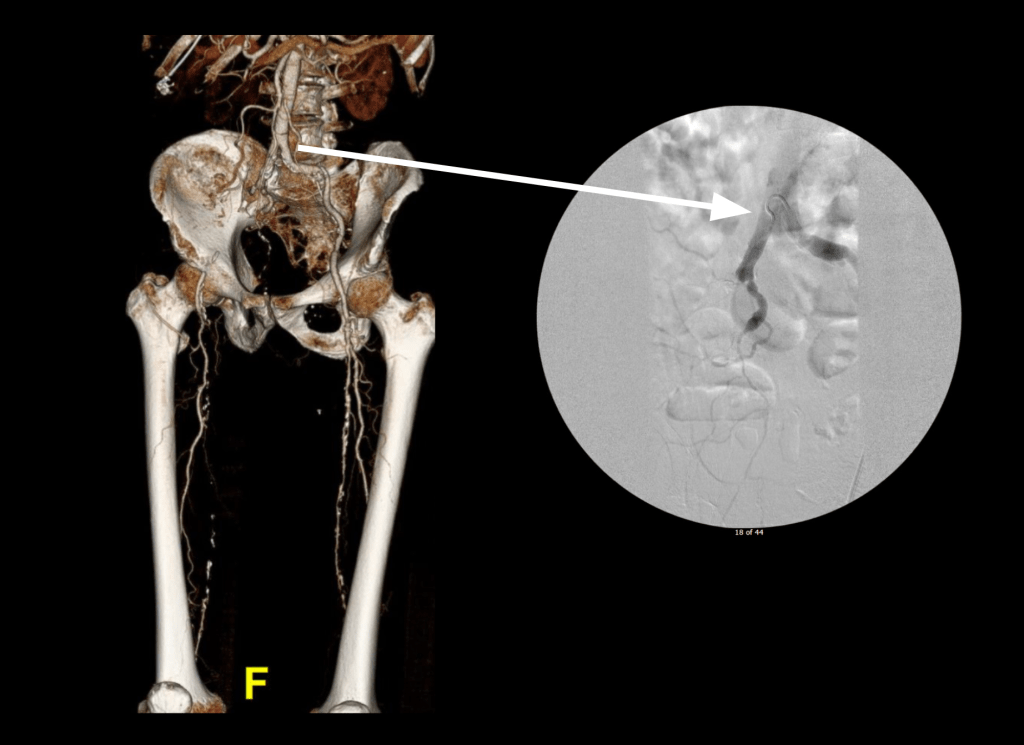

Let me show you one of the first cases I did after returning to Cleveland. I am now practicing at Fairview and Avon Hospitals, premier flagship hospitals in the Cleveland Clinic fleet, on Cleveland’s west side, and a patient arrived while I was on call with sudden onset of pain in his leg from a lack of blood flow. He had occlusive atherosclerotic plaque extending from his external iliac artery to the above knee popliteal artery causing ischemic rest pain.

I contacted LeMaitre Vascular and got in touch with your representative, L. Fisher, who promptly sent the Moll Ring Cutters I needed to perform a remote endarterectomy of the patient’s occlusive external iliac and superficial femoral artery plaque. The technical details of remote endarterectomy are have been covered in my blog (https://vascsurg.me/?s=endore), but in the end, through a 7cm incision in the groin (don’t believe the hype, this is minimally invasive), I restored his arteries to their original open condition. Shown below are the results. It was with great sadness that I heard that the LeMaitre Vascular equipment being sent were the last of the stock available in North America. The patient did very well, with the operation completed well before lunch, and is recovering rapidly from his small wound and big rescue. He gets to walk out of the hospital on two legs, but also with the surety that he avoided a major bypass operation, and avoided the short term gains of stenting from the aorta to the profunda -more peel packs and landfill items and a dubious long term durability. Hey, I even used a XenoSure patch on the common femoral.